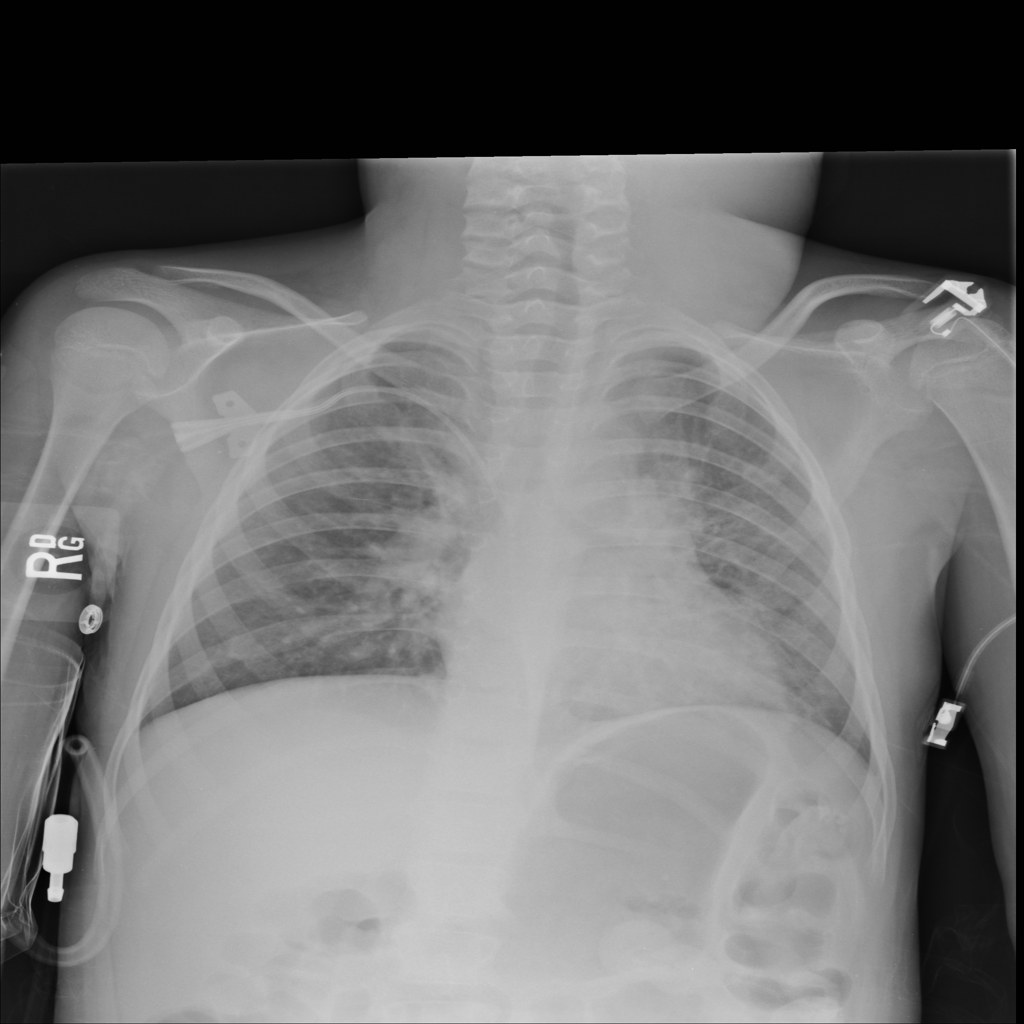

PAT-5B86 · IMG-009Edema

PAT-5B86 · IMG-009

PA